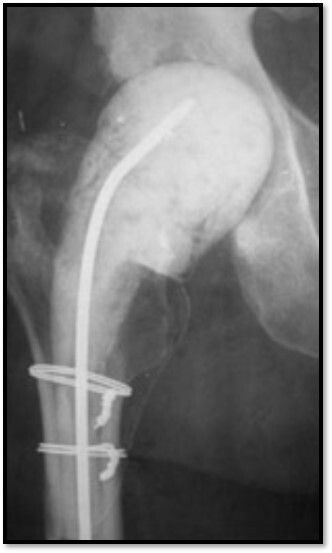

Infected arthroplasty

What is this showing here?